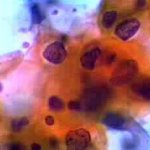

Δυσπλασίες τραχήλου μήτρας σοβαρού βαθμού (CIN III)

Ασυμπτωματική ασθενής 39 ετών. PH κόλπου 4,4. Κολποσκόπιση:

Στην δοκιμασία οξικού οξέως και στην δοκιμασία Lugol, αρνητική περιοχή, τόσο στο πρόσθιο, όσο και στο οπίσθιο χείλος του τραχήλου, σε ακτίνα 3-4 χιλ. και πλάτος περίπου 5 χιλ., με εικόνα διακριτικού επίπεδου μωσαϊκού.